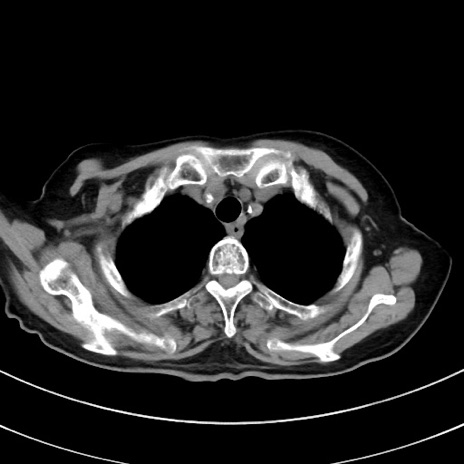

症例33(横断像)

【症例】70歳代 女性

【主訴】心窩部痛

【現病歴】延髄病変の精査・加療にて神経内科入院中。本日より心窩部痛あり。

【既往歴】虫垂炎

【身体所見】右下腹部を中心に圧痛と反跳痛あり。

【データ】WBC 10900、CRP 0.02